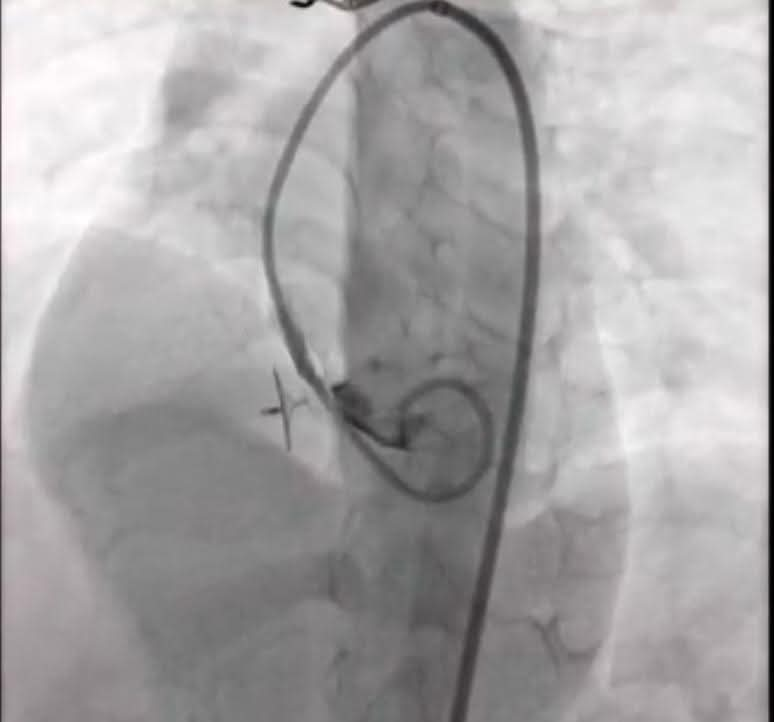

شملت الحالة الأولى طفلًا يبلغ من العمر خمس سنوات من محافظة كفر الشيخ يعاني من تضخم بعضلة القلب بسبب ثقب بين البطينين وتم غلق الثقب بنجاح باستخدام القسطرة التداخلية أما الحالة الثانية فكانت لشاب يبلغ 16 عامًا من محافظة الغربية يعاني من آثار جلطة سابقة وتم غلق ثقب خلقي بين الأذينين ليخرج الطفلان في حالة مستقرة ونتيجة مثالية.

شارك في العملية فريق طبي متكامل من أساتذة القلب والتخدير والعناية المركزة بالإضافة إلى تمريض المستشفى وفنيي الأشعة مما يعكس مستوى الخبرة والكفاءة التي وصلت إليها مستشفيات جامعة طنطا في التعامل مع أصعب الحالات الطبية للأطفال.